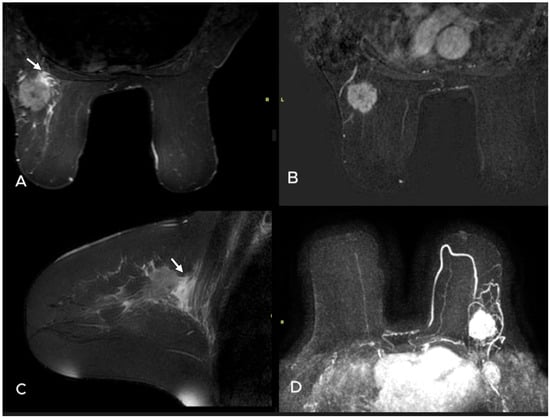

- Uematsu, T. Focal breast edema associated with malignancy on T2-weighted images of breast MRI: Peritumoral edema, prepectoral edema, and subcutaneous edema. Breast Cancer 2015, 22, 66–70. [Google Scholar] [CrossRef]

- Akdoğan Gemici, A.; Tokgoz Ozal, S.; Hocaoğlu, E.; Arslan, G.; Sen, E.; Altınay, S.; İnci, E. Relation of peritumoral, prepectoral and diffuse edema with histopathologic findings of breast cancer in preoperative 3T magnetic resonance imaging. J. Surg. Med. 2019, 3, 49–53. [Google Scholar]

| Presence of edema n (%) | 0.001 * | ||

| None | 17 (48.6) | 14 (15.9) | |

| Peritumoral edema | 14 (40.0) | 43 (48.9) | |

| Diffuse edema | 4 (11.4) | 31 (35.2) | |